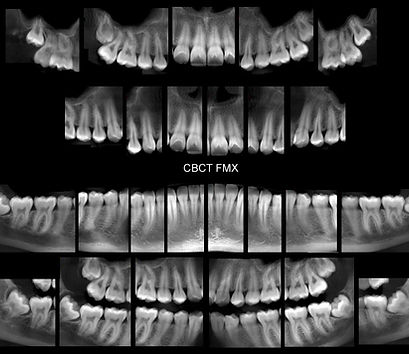

3D CBCT IMAGING

Every CBCT scan is post processed by our highly trained staff. They are experts in CBCT image capture, data management, image formation, and 3D post-processing techniques. Our image surveys support all dental modalities with the best diagnostic image surveys for any CBCT machine.

TYPES OF SURVEYS AVAILABLE

Orthodontic Surveys

Implant Surveys

Orthognathic Surveys